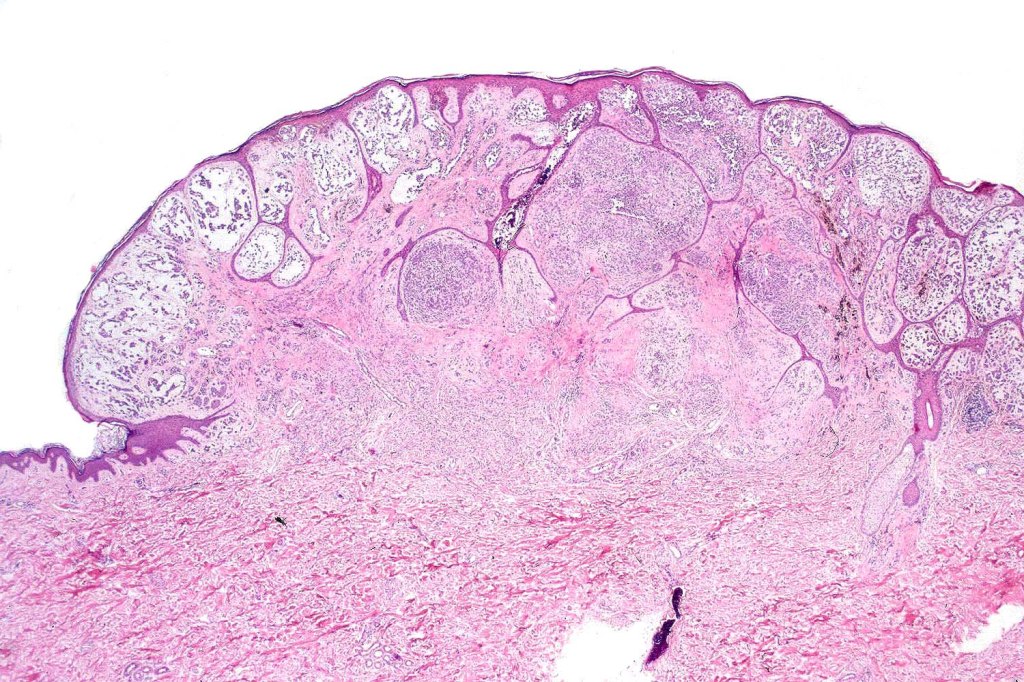

A rare variant of melanoma in which stromal cells produce excess acid mucopolysaccharides inprting a striking myxoid quality. The mucin is Alcian blue & colloidal iron positive, DPAS negative and the melanoma cells stain with typical markeres including S100 & HMB45. It may be seen in primary, recurrent or most often in metastatic lesions. The tumor cells are typically small although occcasionally they are epithelioid. Melanin is often sparse or even avsent making diagnosis difficult. In some examples, a pseudoglandular appearance is seen.

The differential diagnosis is very wide and can include numerous myxoid soft tissue tumors and epthelial mucin-secreting carcinomas. Diagnosis depends on clinical history, mucin stains and the judicious use of immunohistochemistry.